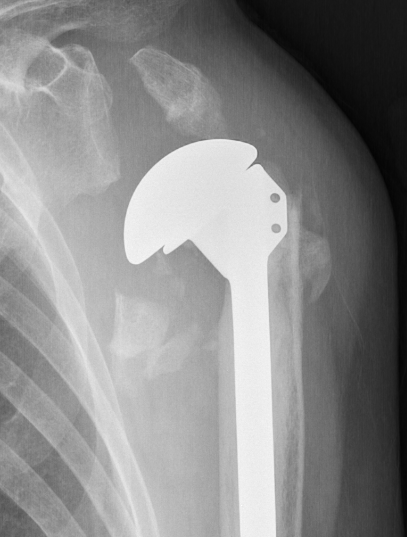

Arthroplasty options

Reverse total shoulder arthroplasty

- elderly patients

- better outcomes than hemiarthroplasty

Hemiarthroplasty

- young patients with unreconstructable fractures

- too young for rTSA

Indications

Unreconstructable fracture in elderly > 65

- comminuted, 3 or 4 part

- head spltting fracture

- off ended / 100% displaced

Unreconstructable fracture - 4 part, comminuted, head spltting fracture

Insufficient glenoid

Patients too young for rTSA